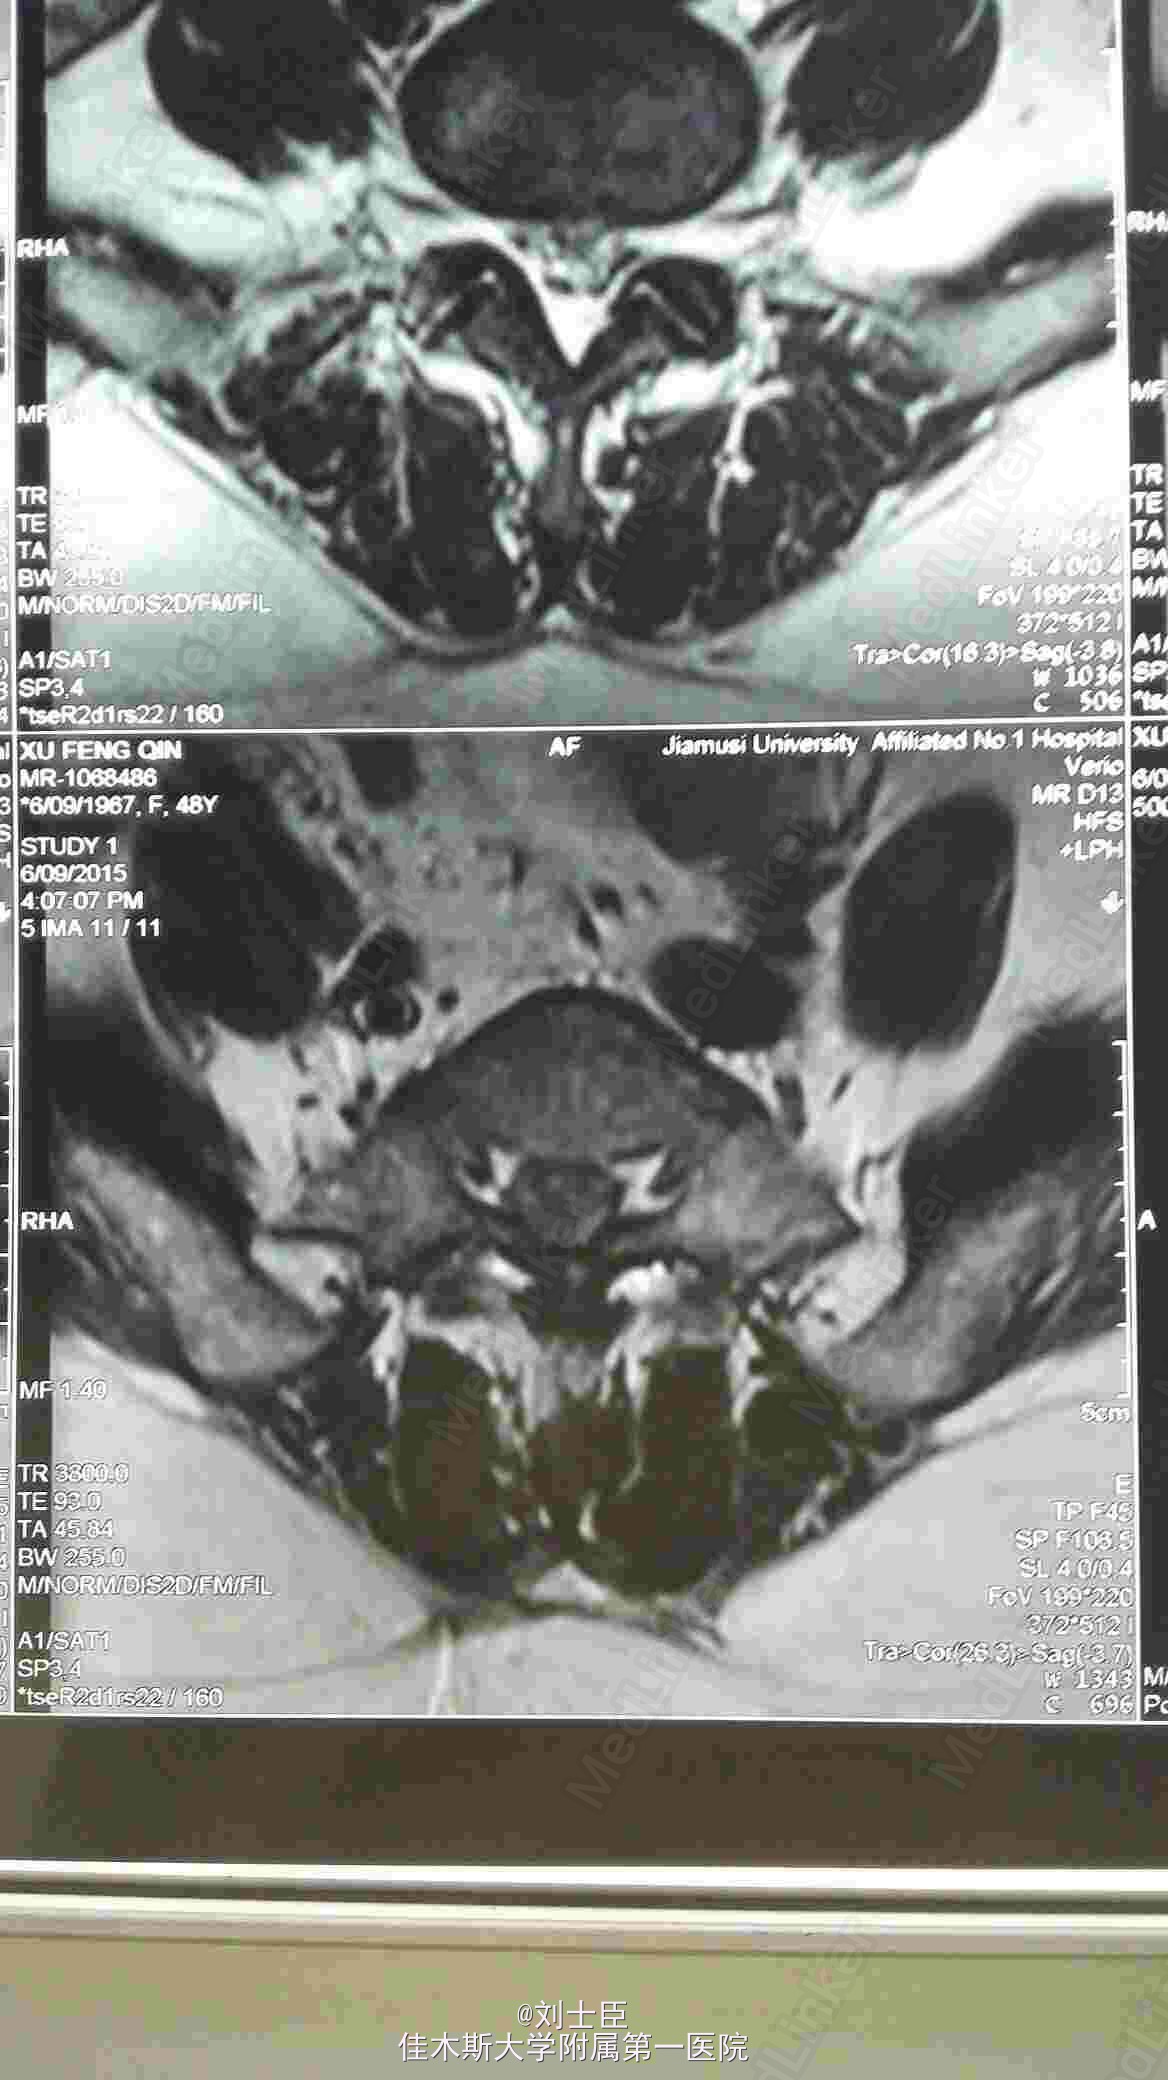

某某,女,43岁。腰痛伴双下肢疼痛1年伴二便失禁7天。

双侧小腿外侧双足及双臀部感觉麻木,双膝反射弱,双踝反射为引出。双下肢肌力进正常。

腰5骶1间盘突出症。马尾综合征。椎间孔镜下游离间盘摘除术纤维环成形术。

病人术后即可刻下地行走自如,直腿抬高实验阴性。3天后拔出尿管,二便正常,双下肢和臀区感觉麻木减轻。